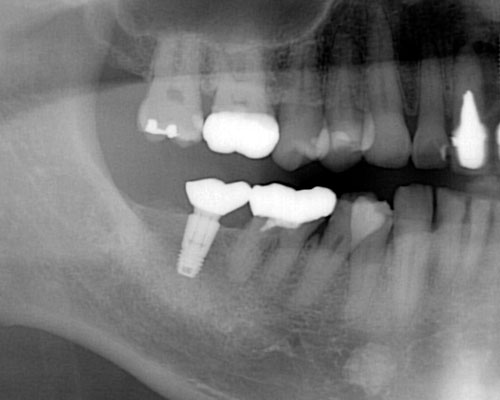

しかし、ここで多くの方が見落としているポイントがあります。ブリッジや入れ歯を入れても、歯の根が増えるわけではないので、残っている歯の負担を軽減することはできません。これが、インプラントなら新たな支えとなるため、残っている歯の寿命を縮めることはなくなることです。

ここで確認しておきたいことがあります。当院で歯を抜く理由の2割が「虫歯」で、2割が「歯周病」です。残りの6割近い原因をご存知ですか?答えは、「破折」です。様々な理由で歯を割ってしまうのです。これは、意外と知られてないことです。そのため、歯に過剰な力がかかることに対する対策を全く考えていない方が多いのです。

言い換えれば、失った歯を補うときには、「虫歯リスク」や「歯周病リスク」にくらべ、全体の6割近いウェートで「力のコントロール」について考慮すべきなのです。(「力のコントロール」については別の記事で解説しますが、インプラントを入れる前、あるいは歯の治療をする前には必ず理解しておいて頂きたい内容ですので是非ご覧下さい。)

インプラントを入れるには割り切って考えることが必要です。インプラントは完全なものではありません。天然歯に比べて多くのリスクを抱えています。しかし、たとえ10年しかインプラントが保たなかったとしても、その10年間はインプラントが噛む力を負担して、他の歯にかかる力を軽減し、歯の寿命を延ばしてくれたと評価することができれば、インプラントを入れた意味は十分にあると思います。